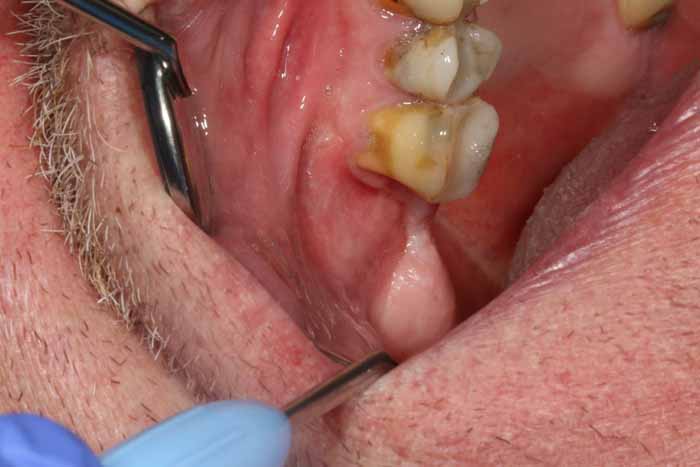

治療

慢性副鼻腔炎の治療には、歯の感染の除去が含まれます。これには、歯内療法、歯周治療、または外科的な処置による抜歯が必要になる場合があります。感染の予防が困難な場合は、抜歯が必要になる場合があります。その後、副鼻腔の交通を特定するために、Vamevalテストを実施する必要があります。患者との良好なコミュニケーションが極めて重要であり、治癒を確実にするためには、より根本的な治療が必要になる場合が多いです。急性副鼻腔炎の場合は治療が必要です。PC予防と、ネザリルなどの充血除去薬を組み合わせた、1回限りの手術が行われる。より大きな交通や瘻孔が慢性化している場合は、鼻の矯正手術(画像4a~4e)が必要となります。場合によっては、耳鼻咽喉科医によるFESS手術と同時に行うこともできます。FESS手術では、鼻の側壁にある開口部を外科的に広げて換気を確保し、閉塞を防止します。

予後

予後は比較的良好ですが、感染が治まった後も鼻づまりなどの症状が長期間続く場合があります。副鼻腔の環境と解剖学的構造が影響を受ける可能性があり、回復に時間がかかる可能性があります。口腔内の閉鎖が完全に達成され、持続的な上顎洞口腔瘻の兆候が見られない限り、さらなる検査と治療のために耳鼻咽喉科専門医への紹介を検討する必要があります。